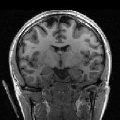

To compare the proposed approach to the mSENSE333SENSE reconstruction implemented by the Siemens scanner, software ICE, VB 17. one, Fig. 1 illustrates coronal anatomical slices reconstructed with both algorithms while turning off the temporal regularization in 4D-UWR-SENSE, so resulting in the so-called 3D-UWR-SENSE approach. Red circles clearly show reconstruction artifacts and noise in the mSENSE reconstruction, which have been removed using our 3D-UWR-SENSE approach. Comparison may also be made through reconstructed slices for and , as well as with the conventional acquisition (). This figure shows that increasing generates more noise and artifacts in mSENSE results whereas the impact on our results is attenuated. Artifacts are smoothed by using the continuity of spatial information across contiguous slices in the wavelet space. Depending on the used wavelet basis and the number of vanishing moments, more or less (4 or 8 for instance) adjacent slices are involved in the reconstruction of a given slice. For instance, using Symmlet filters of length 8 (4 vanishing moments) as in the conducted experiments here, 8 adjacent slices are involved in reconstructing a given slice. However, it is worth noticing that the introduced smoothing is anisotropic, in contrast to standard Gaussian smoothing that could be applied to anatomical data. Fig. 1 also compares 3D-UWR-SENSE and mSENSE reconstructed slices when applying additional spatial smoothing to the later with a mm3 Gaussian kernel. Comparisons clearly show that, even at such low spatial smoothing level, mSENSE images suffer from a significant blur. Moreover, the artifact present at for mSENSE (left red circle) is spread out but not fully removed by applying isotropic spatial smoothing.

Even for slice-selective acquisition schemes where the signal is supposed to be independent between adjacent slices, the proposed algorithm still allows us to exploit information continuity across slices which results from the imaged anatomy. Moreover, the smoothing level strongly depends on the regularization parameters that are used to set the thresholding level of wavelet coefficients. Images reconstructed using our algorithm present higher smoothing level than mSENSE without altering key information in the images. When carefully analysing the image background, one can notice the presence of motion-like artifacts that only affect the background and do not alter the brain mask. Such artifacts are nothing but boundary effects that are due to the use of wavelet transforms.